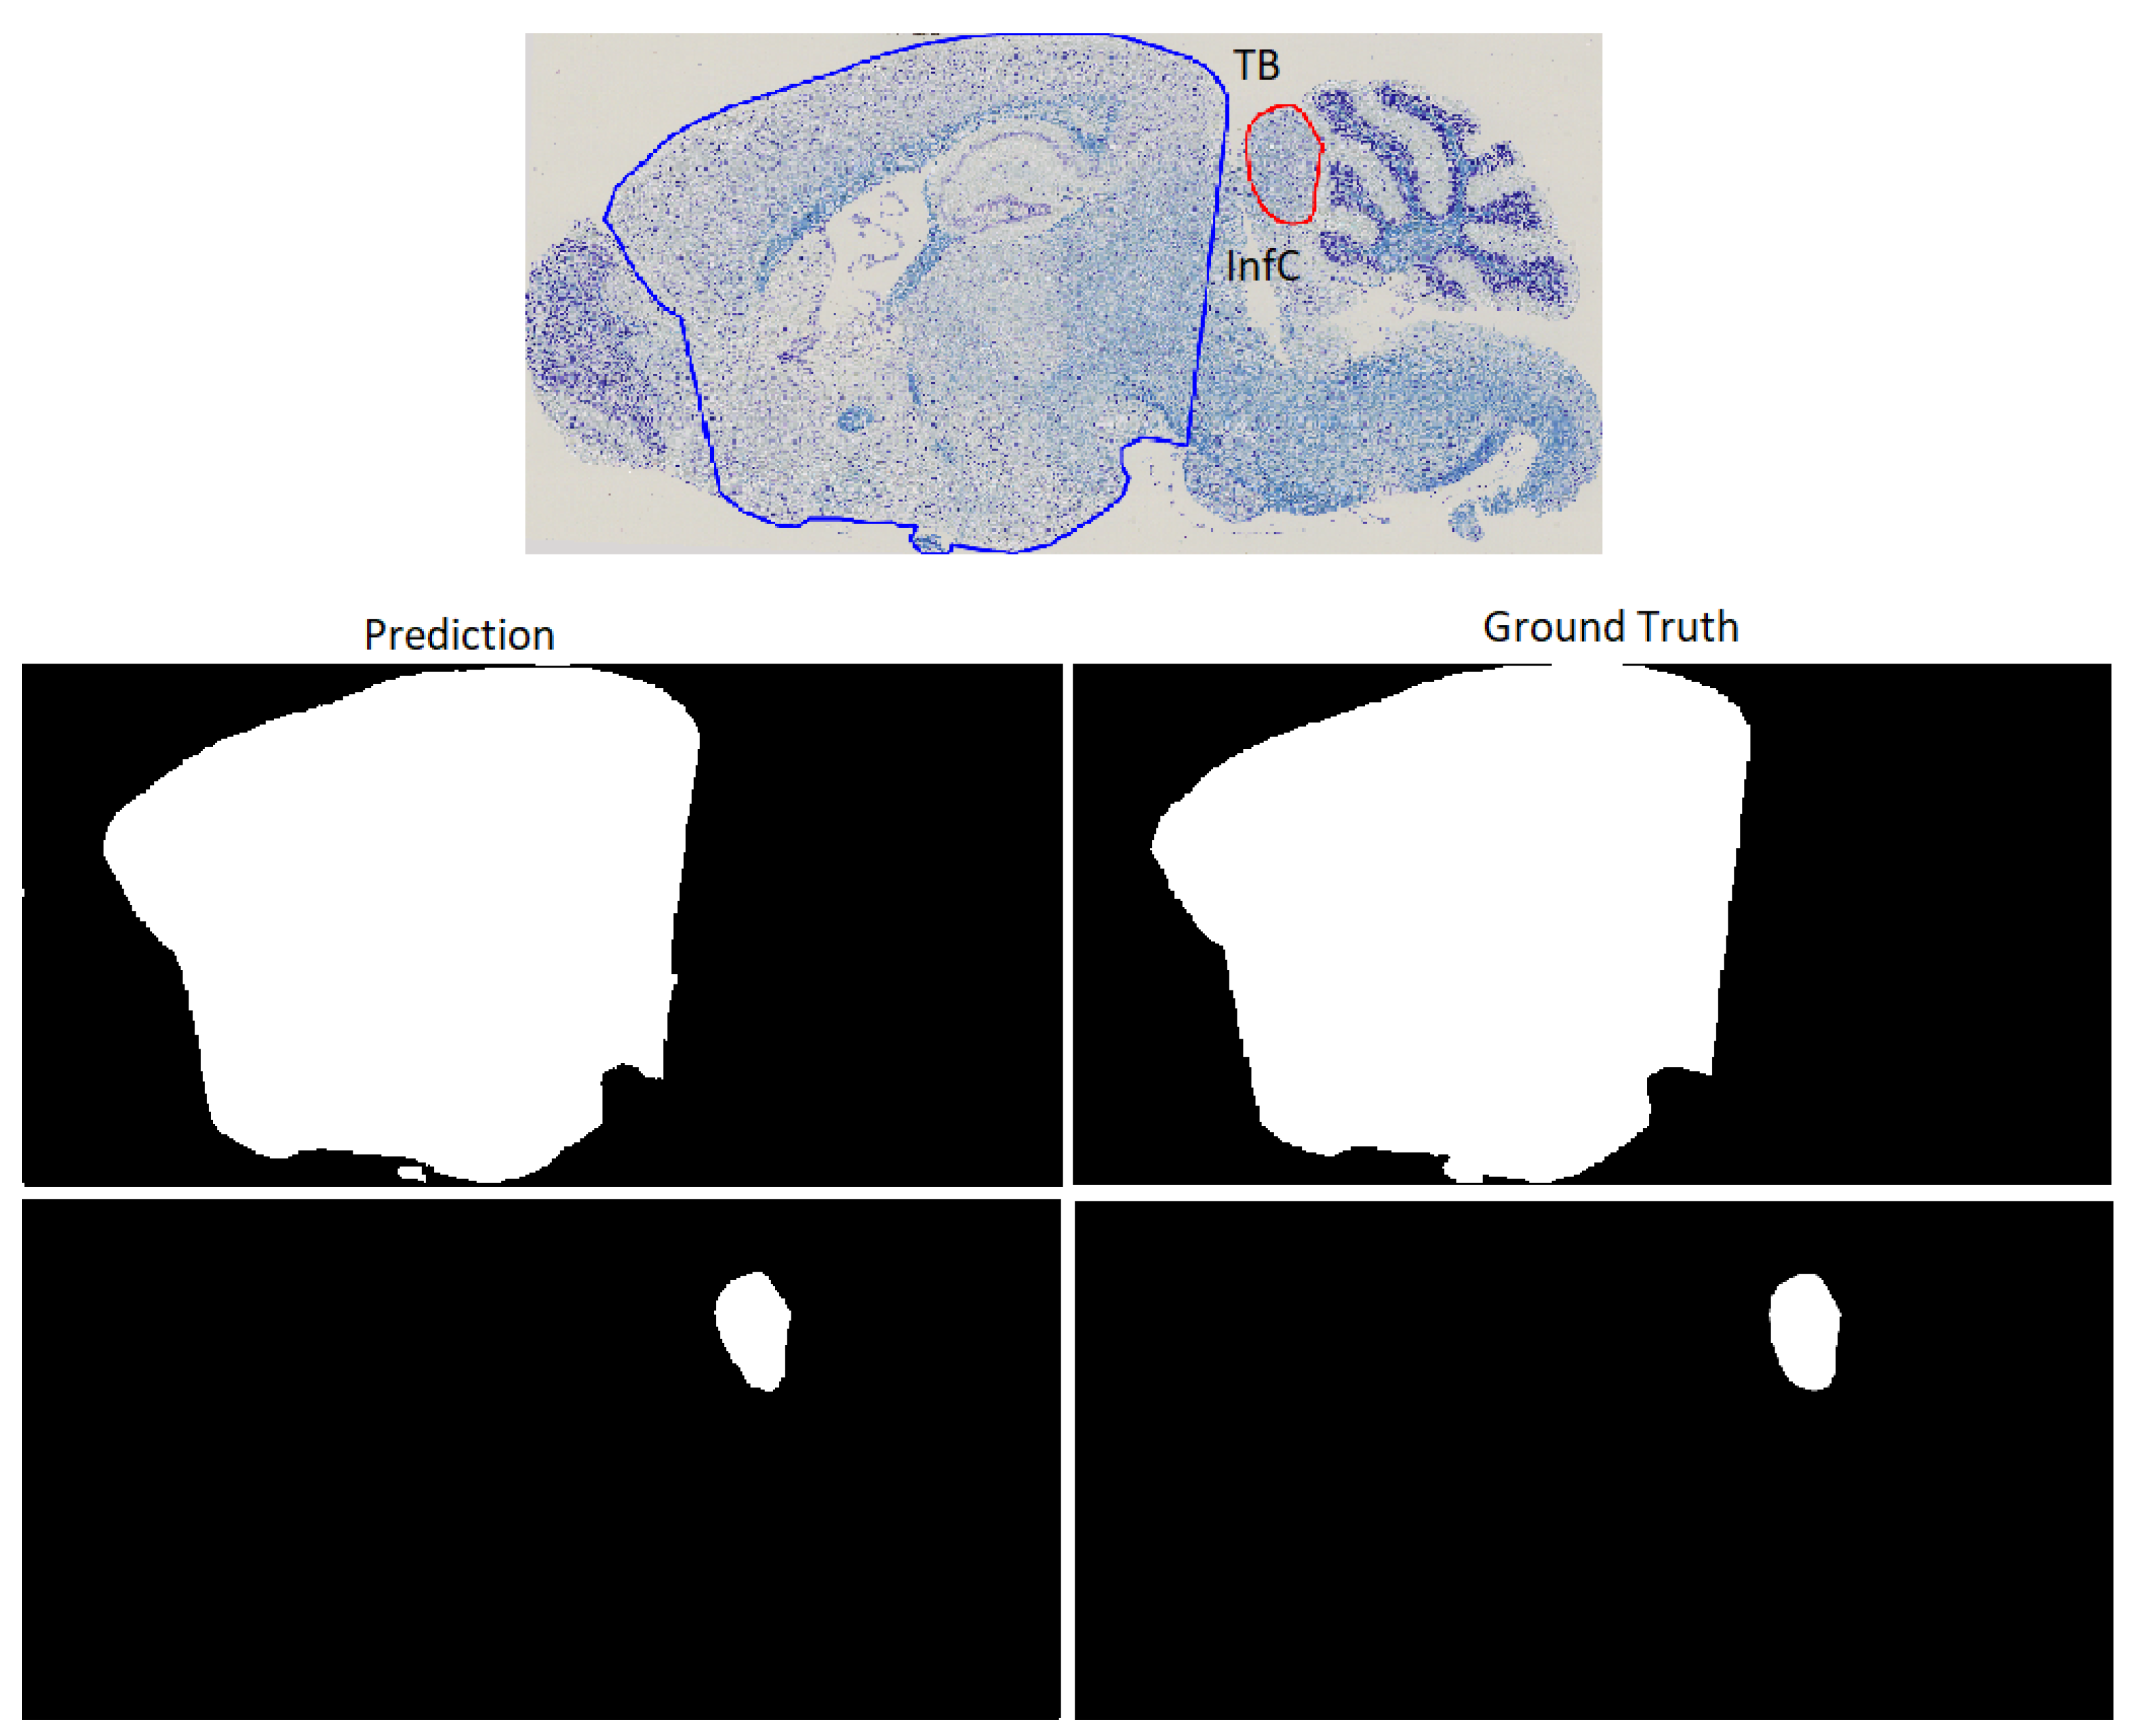

| TB | 0.9914 ± 0.0062 | 0.0079 ± 0.0085 | 0.0078 ± 0.008 | 42.9213 ± 42.1242 |

| InfC | 0.9442 ± 0.0613 | 0.0006 ± 0.0005 | 0.0542 ± 0.0784 | 19.608 ± 13.8624 |